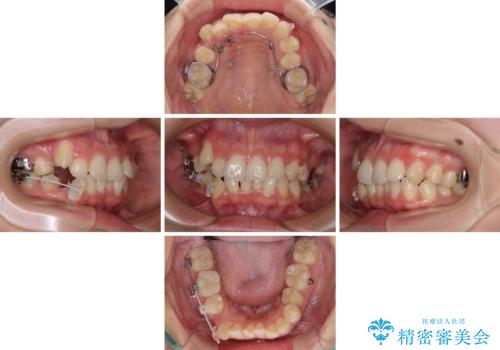

- インビザライン・審美装置

- 2年10ヶ月

骨格的に下顎が左側に変位していたため、上下正中を合わせることは困難であることは分かっていましたが、可能な限り合わせることができました。

骨格的なズレがあると仕上げの段階で奥歯の咬み合わせが不安定となるため、予定よりやや長期間となりました。